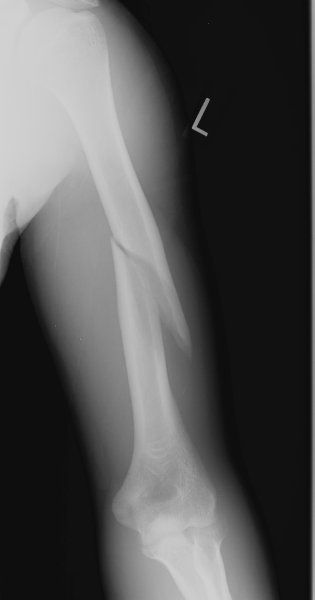

- X-ray (AP and lateral views): Confirms the fracture and displacement

Fracture of the neck of the humerus is a common upper-limb injury, especially in elderly individuals with osteoporosis and in younger adults following high-energy trauma. It involves a break near the proximal end of the humerus, close to the shoulder joint, and can significantly affect shoulder mobility and function. Early diagnosis and appropriate physiotherapy play a key role in recovery.